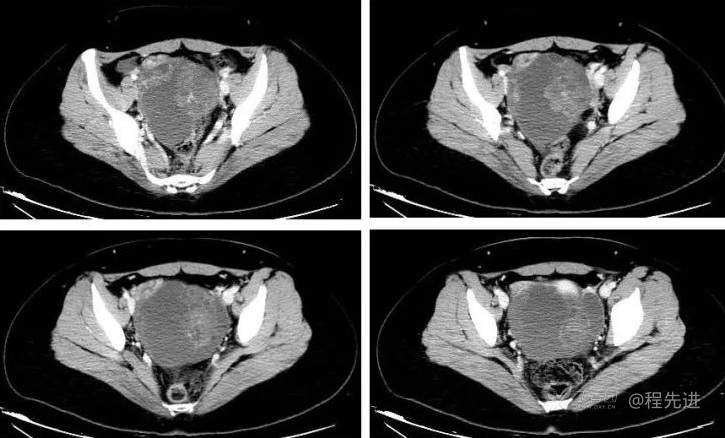

阴式彩超:子宫前位,大小47*51*28mm,形态规则内膜厚7mm。左侧类似卵巢大小32*27mm,右侧卵巢大小25*18mm,子宫偏右侧可见105*94*76mm混合回声包块,与右侧卵巢分界不清,有包膜,内以液暗区为主,夹杂可见范围约51*40mm不规则稍高回声团,隐约可见将类似左侧卵巢包裹其中。另子宫偏左侧可探及一大小38*32mm囊性肿块,边界清,壁薄光滑,内透声好,后壁效应增强。CDFI: 混合回声包块未见明显彩流。囊性肿块内未见明显血流信号。盆腔内子宫直肠窝探及23mm液暗区

提示:子宫偏右侧混合回声包块,疑占位性病变,炎性包块待排,子宫偏左侧囊性肿块,盆腔积液。